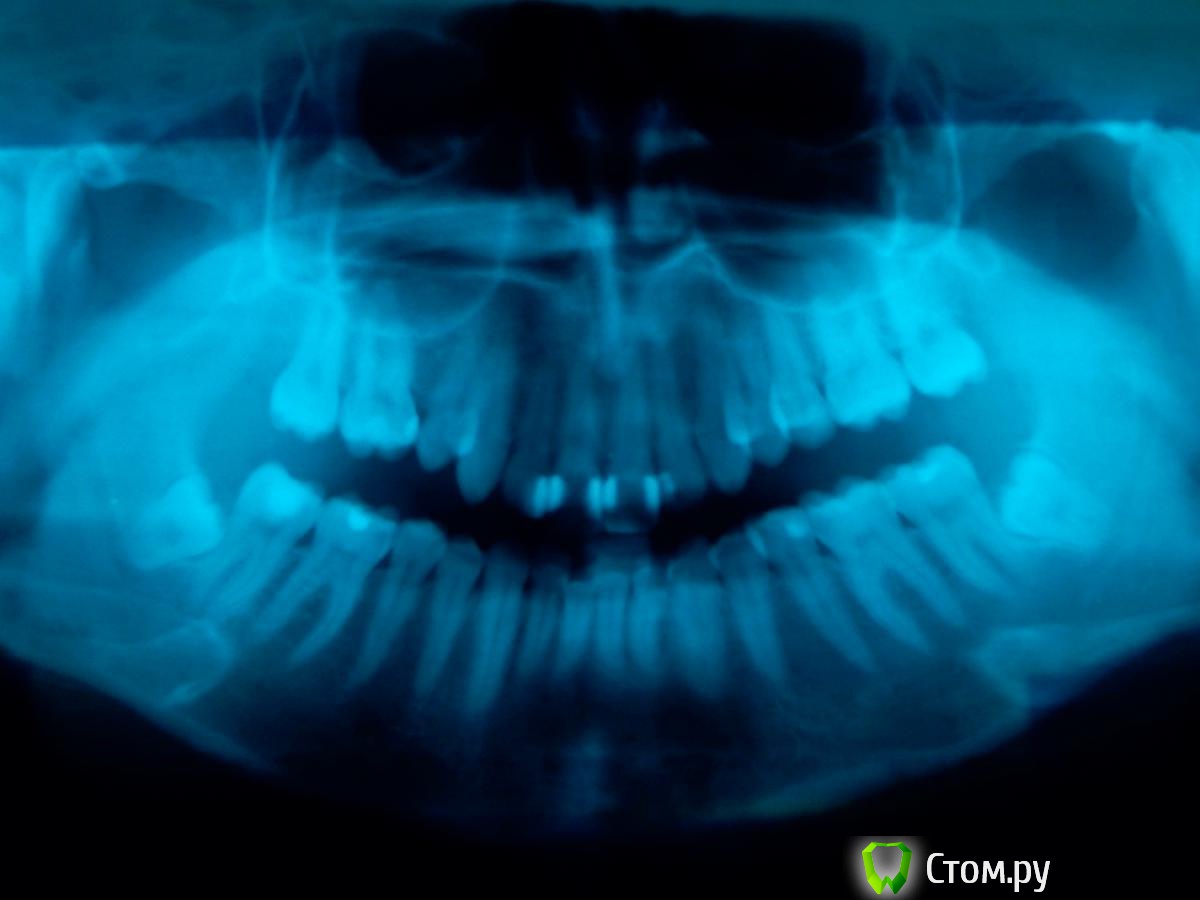

Эльzа Опубликовано 3 мая, 2014 Поделиться Опубликовано 3 мая, 2014 Добрый день, Проконсультируйте, пожалуйста, на тему удаления восьмерок. Заняться данным вопросом меня вынудила боль в нижней левой 7ке – сначала просто постоянная ноющая (довольно сильная, пила обезболивающие), через пару дней трансформировалась в острую простреливающую при даже минимальном соприкосновении 7ки с верхними зубами. Сейчас на 7ку я могу осторожно жевать и даже слегка клацать зубами, не болит. Это так сказать вводная. Теперь основное. Снимок снял подозрения о проблеме под пломбой с 7ки и обозначил необходимость удаления 8ки (даже без привязки к боли в зубе). Консультировалась с несколькими специалистами, но открытые вопросы все еще есть. А именно:Два рекомендованных хирурга (очень рекомендованных, из гос учреждений правда) назвали данное удаление сложным/очень травматичным и сориентировали на продолжительность час+, один из них даже рассматривал вопрос амбулаторного удаления.. ответы в похожих темах про 8ки настораживают – у меня вроде бы не всё так плохо и не должна данная манипуляция занимать час+, хотя я не врач конечно Уважаемые, а вы как оцениваете сложность/продолжительность данного удаления? Третий хирург, ввиду очень близкого расположения 8ки к 7ке, сказала, что болезненность 7ки может сохраниться и после удаления 8ки (теперь уже не из-за давления 8ки на 7ку, а из-за оголенных корней 7ки). В общем она порекомендовала сначала депульпировать 7ку, т.к. опасается, что эту процедуру всё равно потом придется делать. Ваше мнение? По самОй процедуре удаления – насколько я понимаю есть 2 варианта – швы или открытая лунка с какими-то там тампонами/лекарствами. В чем смысл и преимущества второго варианта - по описанию он выглядит гораздо менее "удобным"? Что предпочтительнее в моем случае? или это станет ясно по ходу дела? Мне что-то говорили про выдалбливание кости.. если честно неочень помню, в шоке была)) и могу что-то путать, можете прокомментировать – это актуально/необходимо в моем случае? Я правильно понимаю, что со второй 8кой тоже надо распрощаться? Я правильно понимаю, что мне повезло и верхних 8к у меня нет и не будет (мне 29 лет)? И последнее – что за светлые области на снимке – нижняя челюсть, с обоих сторон под 6-7ками?Большое спасибо за ответы! Ссылка на комментарий

diesel87 Опубликовано 3 мая, 2014 Поделиться Опубликовано 3 мая, 2014 Добрый вечер1. С учетом анестезии 30-40 минут максимум2. С оголенными корнями 7-ого думаю ничего страшного не произойдет, а вот кариес корня возможен, но тоже под вопросом, я бы сначала убрал явную причину (8-ку), а через неделю бы оценил ситуацию3. Я бы предпочел и предпочитаю швы, считаю надежнее4. Выдалбливание это грубо сказано) распил коронки 8-ого и может чуть косточку за ним зацепить, но главное слово то "распиливание"))5. Да6. Да, возраст уже не важен, их просто НЕТ) и не будет)7. Пальцы рентгенлаборанта)) (наслаивание других костных структур) 3 Ссылка на комментарий